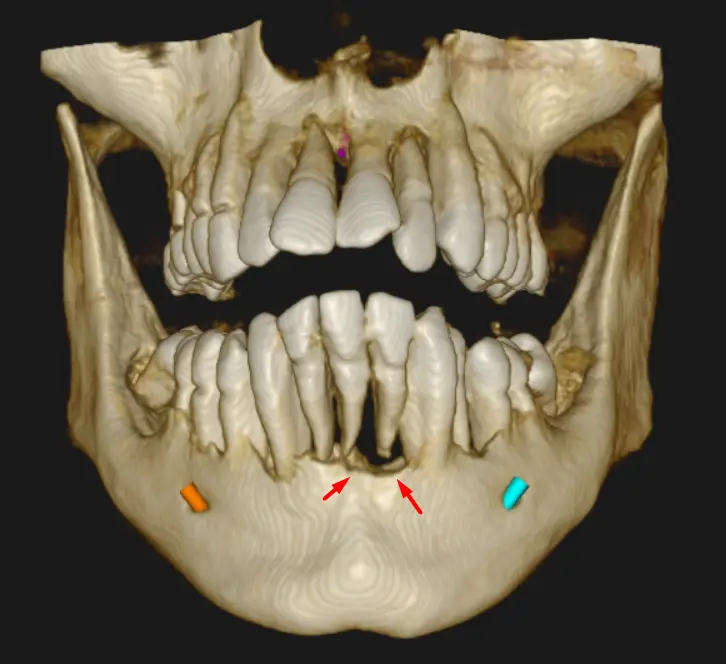

En una vista panorámica (ver Fig 1) se evidencia pérdida ósea alveolar generalizada, afectando ambos maxilares. El nivel óseo se encuentra significativamente descendido respecto al tercio cervical de las raíces dentarias, compatible con un proceso periodontal avanzado.

Se observa disminución marcada del soporte óseo alrededor de múltiples piezas, con exposición radicular extensa como el caso de las piezas dentarias 46 y 38, ver cortes tangenciales (ver Fig 2 y 3), lo que radiográficamente se correlaciona con movilidad dentaria clínica. En algunos sectores se aprecia compromiso óseo severo, con reducción importante de la altura del reborde alveolar.